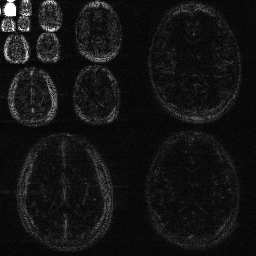

Magnetic Resonance Imaging (MRI) has excellent soft tissue contrast but is hindered by an inherently slow data acquisition process. Compressed sensing, which reconstructs sparse signals from incoherently sampled data, has been widely applied to accelerate MRI acquisitions. Compressed sensing MRI requires one or more model parameters to be tuned, which is usually done by hand, giving sub-optimal tuning in general. To address this issue, we build on previous work by the authors on the single-coil Variable Density Approximate Message Passing (VDAMP) algorithm, extending the framework to multiple receiver coils to propose the Parallel VDAMP (P-VDAMP) algorithm. For Bernoulli random variable density sampling, P-VDAMP obeys a "state evolution", where the intermediate per-iteration image estimate is distributed according to the ground truth corrupted by a zero-mean Gaussian vector with approximately known covariance. To our knowledge, P-VDAMP is the first algorithm for multi-coil MRI data that obeys a state evolution with accurately tracked parameters. We leverage state evolution to automatically tune sparse parameters on-the-fly with Stein's Unbiased Risk Estimate (SURE). P-VDAMP is evaluated on brain, knee and angiogram datasets and compared with four variants of the Fast Iterative Shrinkage-Thresholding algorithm (FISTA), including two tuning-free variants from the literature. The proposed method is found to have a similar reconstruction quality and time to convergence as FISTA with an optimally tuned sparse weighting and offers substantial robustness and reconstruction quality improvements over competing tuning-free methods.